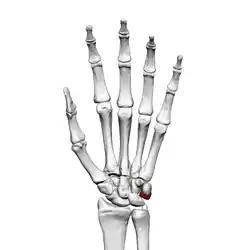

Triquetral bone

The triquetral bone (/traɪˈkwɛtrəl, -ˈkwiː-/; also called triquetrum, pyramidal, three-faced, and formerly cuneiform bone) is located in the wrist on the medial side of the proximal row of the carpus between the lunate and pisiform bones. It is on the ulnar side of the hand, but does not articulate with the ulna. It connects with the pisiform, hamate, and lunate bones. It is the 3rd most commonly fractured carpal bone.

![]() Left hand anterior view (palmar view). Triquetral bone shown in red. | |